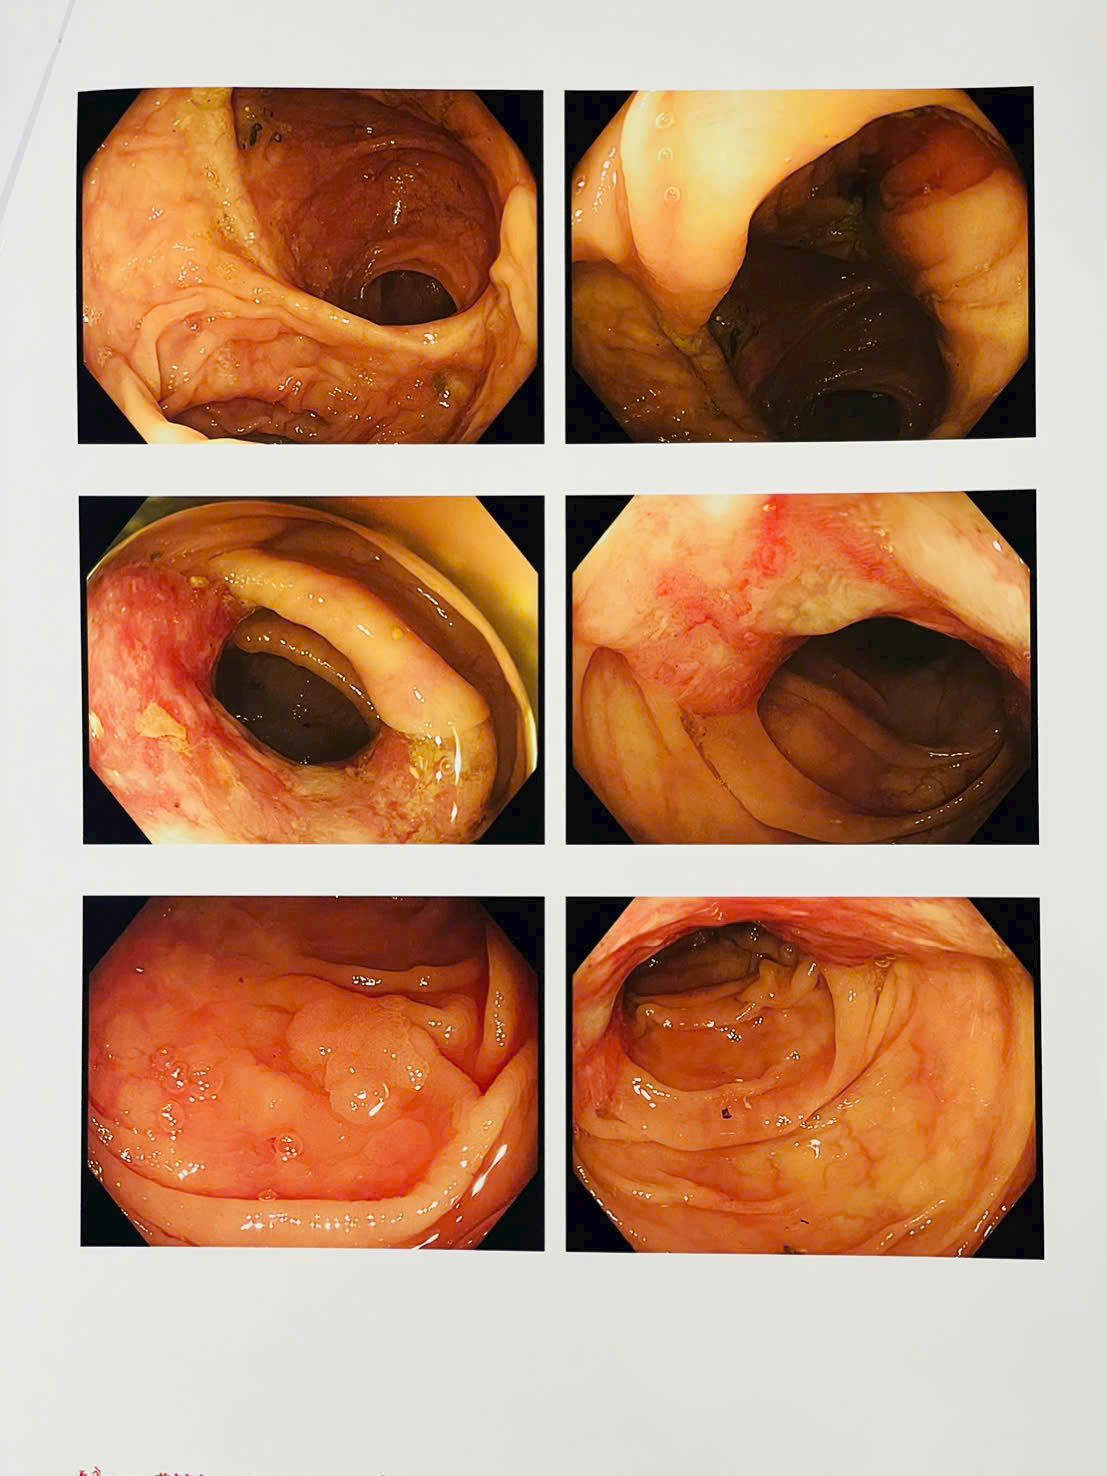

Kết quả xét nghiệm cho thấy bệnh nhân bị thiếu máu nặng, biểu hiện của tình trạng mất máu mạn tính. Trước dấu hiệu bất thường này, các bác sĩ đã chỉ định đánh giá lại toàn diện bằng nội soi dạ dày, nội soi đại tràng, làm các xét nghiệm tổng thể đánh giá nguyên nhân thiếu máu và chụp cắt lớp vi tính (Cắt lớp vi tính 256 dãy) toàn thân. Kết quả phát hiện một khối u sùi mới tại đại tràng, nhiều khả năng là ung thư tái phát (cần kết quả giải phẫu bệnh để chẩn đoán xác định) và rất nhiều polyp đại tràng.

Ung thư có thể tái phát nếu chủ quan sau điều trị- Ảnh 2.

Ung thư có thể tái phát nếu chủ quan sau điều trị- Ảnh 3.